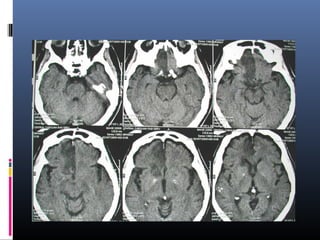

Rt PICA

infarct

SCA infarct